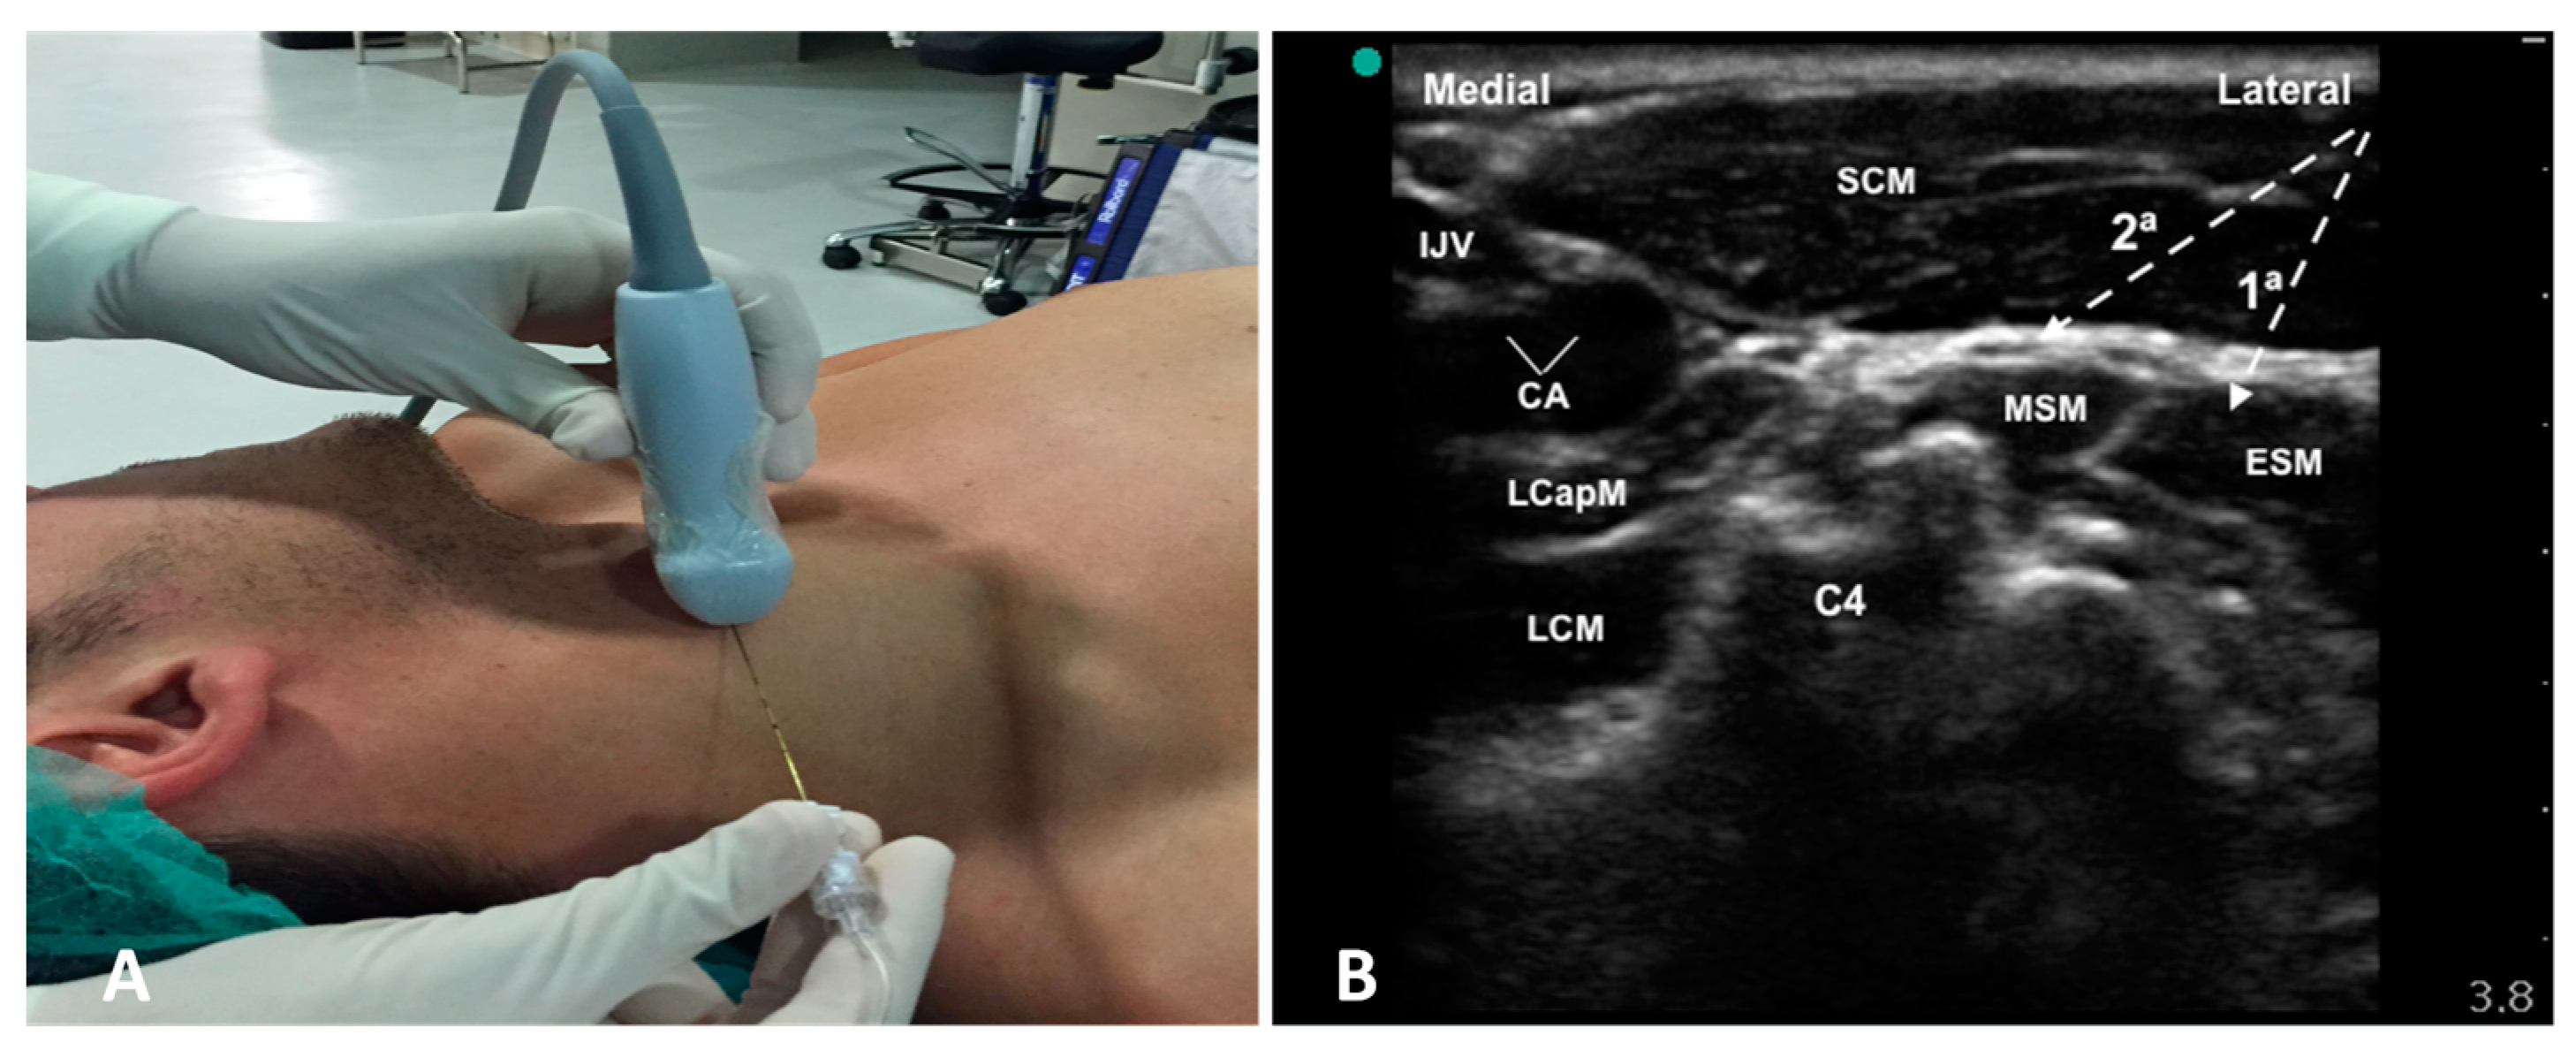

2.1. Anesthetic Technique